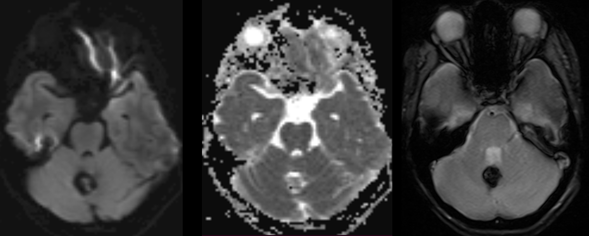

Neurological physical examination and vital signs were normal. A simple skup CT was done showing a mass occupying the cerebellar vermis. Therefore, a contrast-enhanced MRI is performed in which the mass is characterized by having a "popcorn" configuration, with central hyperintensity on T1 and T2 with hypointense halo in all sequences (Figure 1) more evident in gradient echo which is compatible with a cavernoma (Figure 2). It is noteworthy that in the contrasted T1 sequence an DVA is found adjacent to the cavernoma with a subependymal drainage vein (Figure 3).

Figure 2 Axial images with information on DWI, ADC and gradient echo of the cavernoma described in Figure 1. There is no diffusion restriction, with "blooming" on gradient echo.

The MR cavernoma will have the classic hyperintense “popcorn” image on T1, T2 and FLAIR in its center (Figure 1), without restriction on DWI-ADC sequences and with a halo of haemosiderin visible on all sequences, more evident in T2*, with “blooming” artifact in gradient echo (Figure 2).4,6 Isolated ADLs do not require treatment, since obliterating the only drainage system in the territory where they are located can generate a venous infarction.4 If it is part of a mixed vascular malformation, the treatment will be based on the other component, as in our case, the surgical management or follow-up of the cavernoma. That is why it is important for us as radiologists to identify and describe the drainage system that the AVM has.